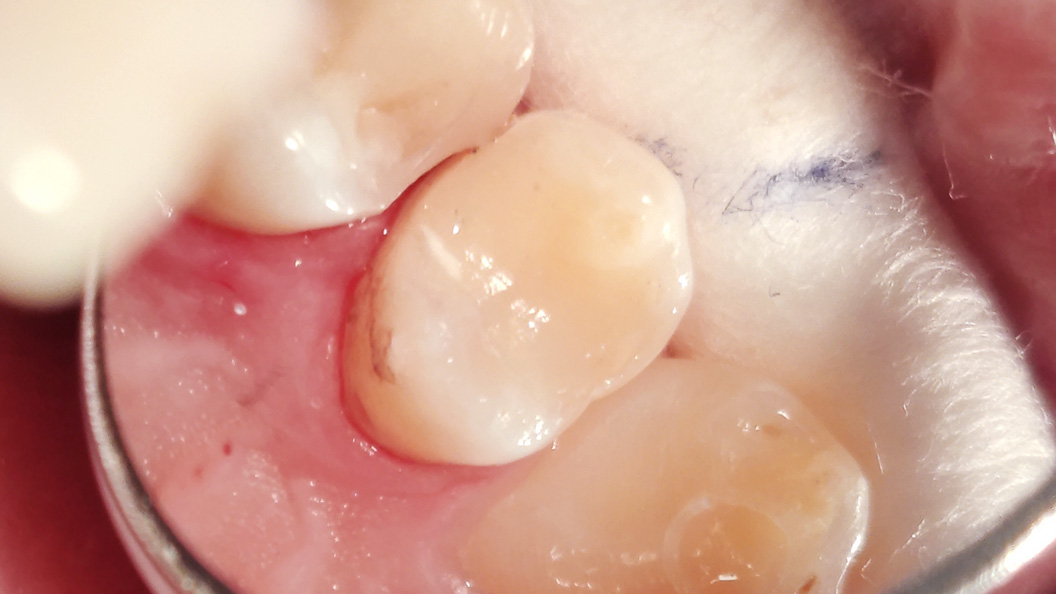

Пациент обратился с жалобами на эстетический недостаток в области правого верхнего зуба. После обработки полости под контролем кариес-маркера была обнаружена полость средней глубины. Дно и стенки плотные, гладкие, блестящие, при зондировании крепетируют. Реакция не перкуссию и холодную пробу безболезненная. Диагноз — хронический средний кариес.

При среднем кариесе кариозная полость находится в пределах эмали и среднего слоя дентина. Если его не лечить, он может стать глубоким. В хронической форме пациент может обратиться к врачу слишком поздно, потому что нет такой интенсивности болевых ощущений, как при острой форме.

Ход лечения:

- применение инфильтрационной анестезии Sol. Articaini vs. Adrenalini 1:200000 1.8 ml;

- наложение системы коффердам;

- механическая обработка кариозной полости;

- медикаментозная обработка полости раствором хлоргексидина 2%;

- наложение пломбы Vitremer (A3);

- микроконтурирование и макроконтурирование пломбы.